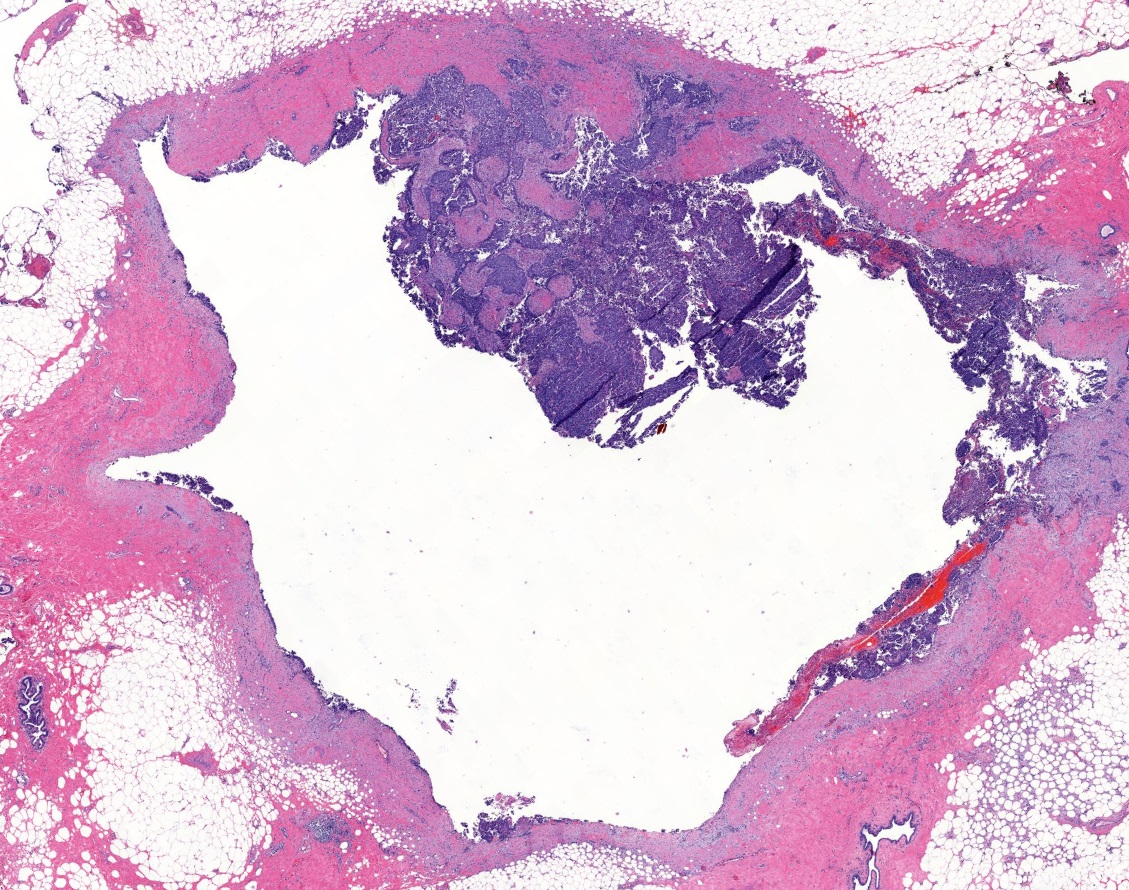

- Papillary tumor with pushing borders, may be within a cystically dilated duct, surrounded by a thick fibrous capsule (Histopathology 2008;52:20, Mod Pathol 2021;34:1044, Virchows Arch 2022;480:5)

- Delicate papillary fronds with fibrovascular cores lined by cuboidal to columnar epithelial cells with low to intermediate grade atypia

- Cribriform and solid architecture may be present

- Most show complete lack of myoepithelial cells along the papillae and around the periphery of the tumor (Am J Surg Pathol 2006;30:1002, Am J Surg Pathol 2011;35:1)

- Invasive carcinoma is defined as the presence of neoplastic cells infiltrating beyond fibrous capsule (Mod Pathol 2021;34:1044)

- Epithelial displacement / entrapment of neoplastic cells within capsule can occur and must be distinguished from true invasion beyond the fibrous capsule

Microscopic (histologic) images

Contributed by Kristen E. Muller, D.O. , Mariel Molina Nunez, M.D. and Julie Jorns, M.D. (Case #518)